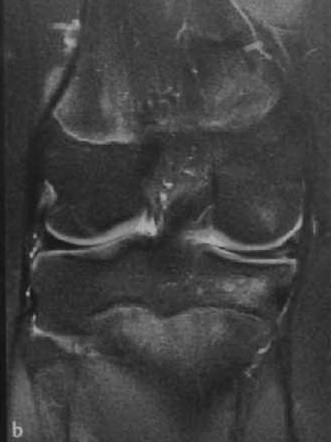

После операции частичного удаления мениска нередко возникают боли в оперированном суставе. тогда стоит вопрос о повторном разрыве. Задача МРТ коленного сустава состоит в дифференциальной диагностика следа восстановления мениска после операции от повторного разрыва. Повышенный сигнал в мениске на Т2-взвешенных МРТ очень схож при заживлении мениска и при разрыве, однако, разрывы обычно линейной формы и связаны с замечательной пластинкой. После операции могут быть также трабекулярные отеки костного мозга, что может отражать остеонекроз.

МРТ коленного сустава. Корональная Т2-взвешенаая МРТ. Нормальное состояние мениска после частичной менискэктомии.